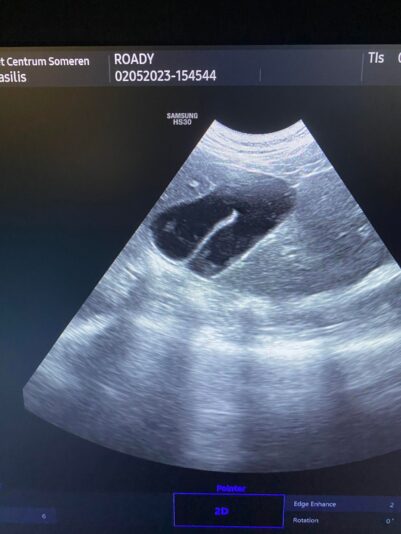

these are the photos of the bloodwork and from the ultrasound

This post is about a patient of mine that came to me on Wednesday.

General information and history: Cat, male, not castrated, 11 years old with different behaviour since 3 days. According with the owners, the cat didnt want to eat and drink for 3 days. Also he wasnt active and he was hiding. The owners didnt have…